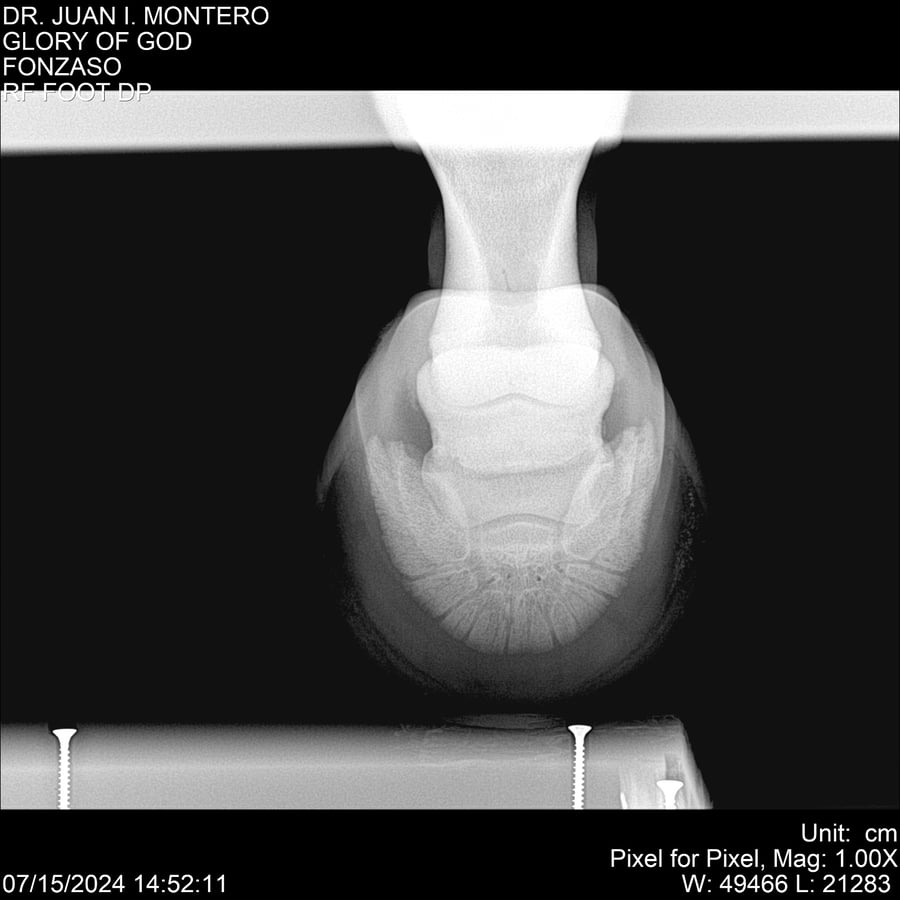

LOTE 10, GLORY OF GOD 🔥 🔥 🔥 Lote Anterior Volver al remate Lote Siguiente Ficha Contacto Montevideo - Ficha del Lote Identificador: #281389 Categoría: Yeguarizos Montevideo - 115 Visualizaciones ClicData Contacto Empresa: Abelenda N. R., Walter Hugo Nombre*: Teléfono* : E-mail* : Mensaje Enviar Registrese gratis Este contenido Exclusivo está disponible sólo para usuarios registrados Ingresar